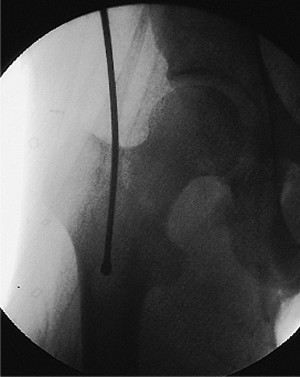

Figure 21.29.

Guide-wire passage past the fracture site. Guide-wire passage into the distal fragment is confirmed. Both AP and lateral views should be taken to assure that the wire is in the medullary canal. |